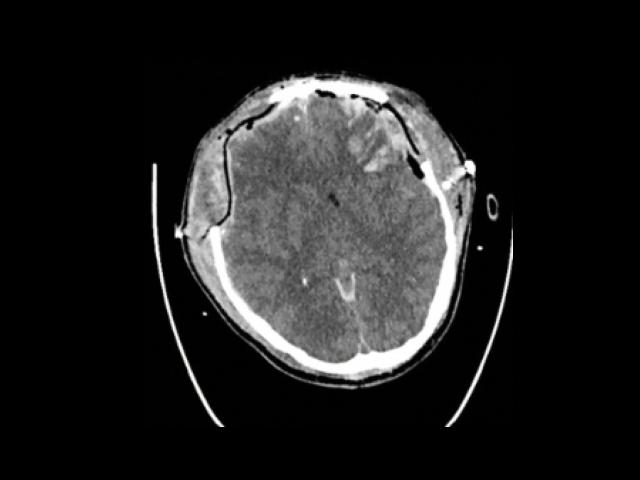

Sample Gallery